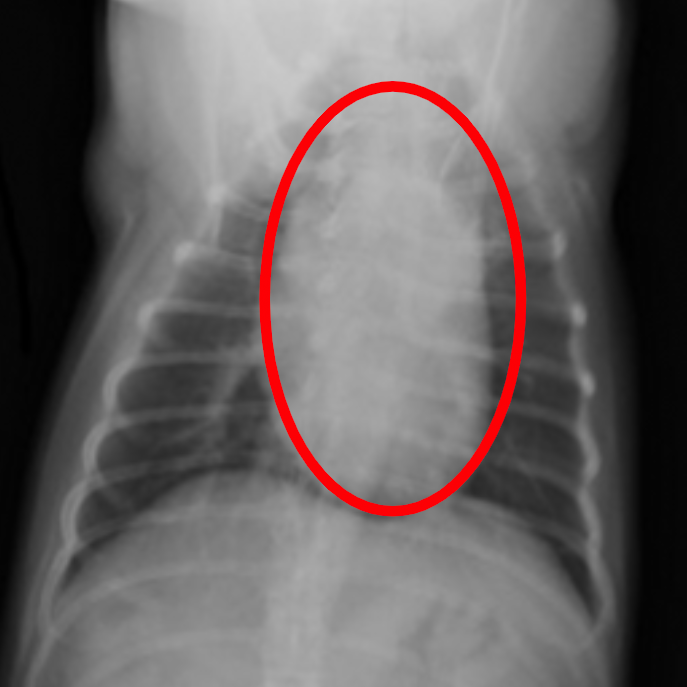

レントゲン検査

心臓の形や大きさ、肺、血管の太さのチェックをします。